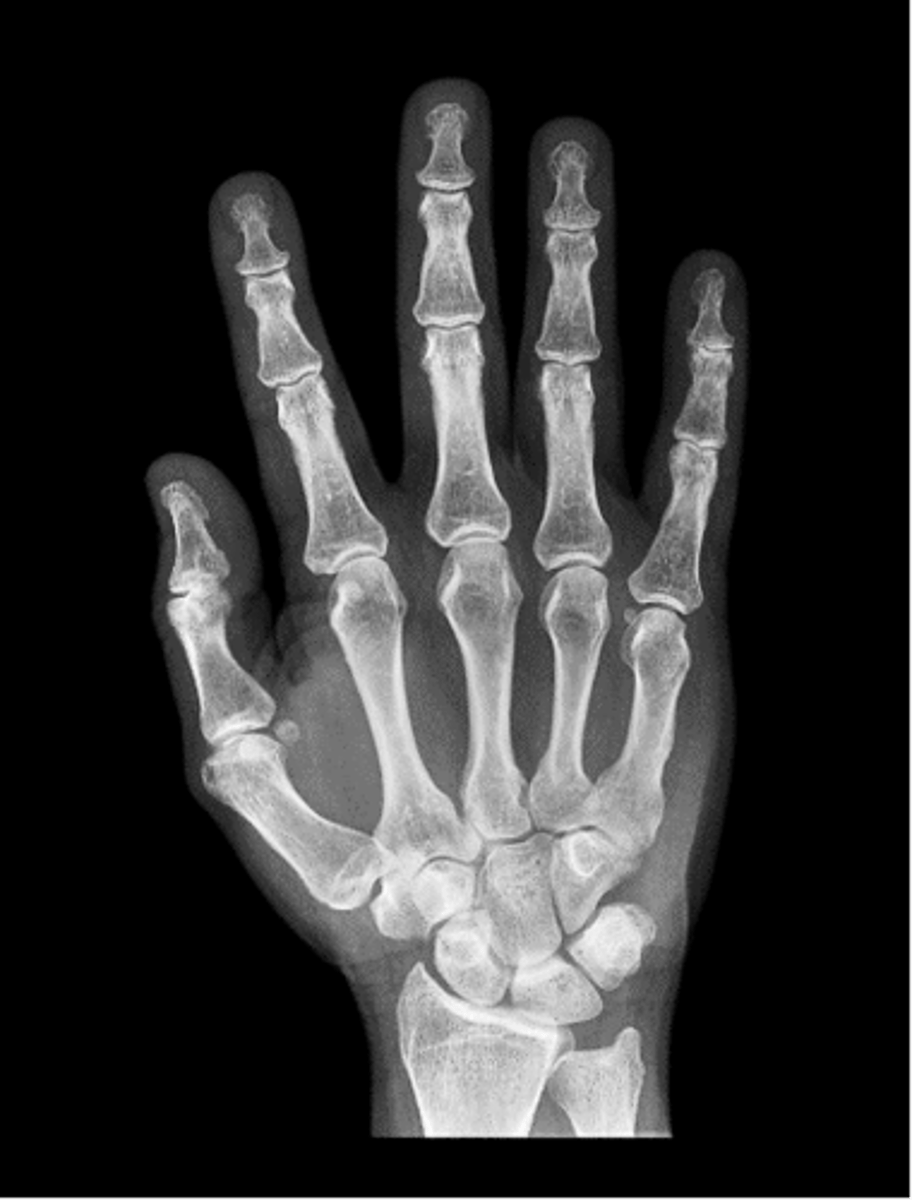

PA hand

PA oblique hand